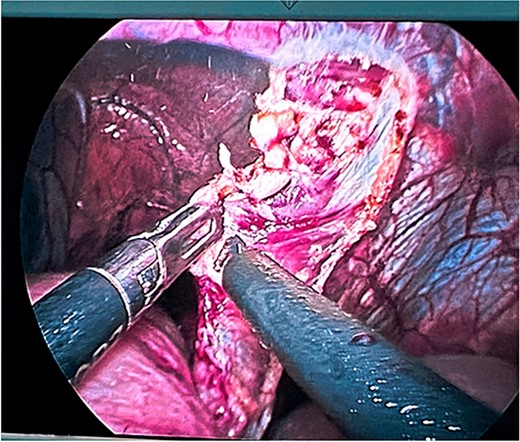

Surgical treatment was decided. Five ports were used: one supraumbilical 12 mm port for the telescope, one 5 mm subxiphoid port for the liver retractor, and three working ports placed in the left midclavicular line of 12 mm, the left axillary line of 5 mm, and the right midclavicular line of 5 mm. A type IV hiatal hernia was found with a 12 cm hernia defect (Fig. 3), a hernia sac measuring 20 cm × 15 cm × 7 cm, containing the entire stomach, dudodenum, pancreas, greater omentum, and transverse colon. The content was reduced to subsequently dissect and resect the hernia sac (Fig. 4).

Reduction of the contents of the hernial sac with intestinal forceps and blunt dissection. Hiatal defect of ~12 cm.

Dissection and resection of hernial sac with traction and monopolar energy.